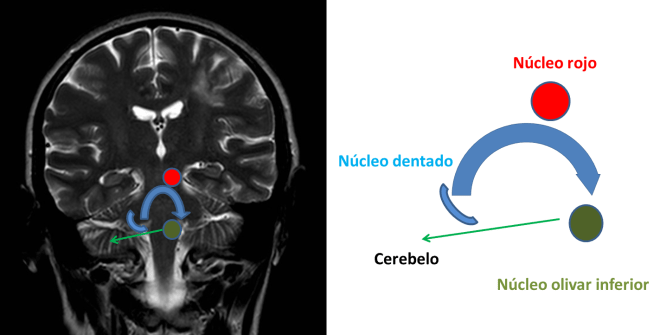

En todos ellos se explica que los vértices del triángulo de Mollaret son el núcleo rojo, el núcleo dentado y la oliva. Y que los lados son tres: 1. Las fibras que desde el núcleo dentado van al núcleo rojo contralateral (dentatorubral) a través del pedúnculo cerebeloso superior; 2. Las fibras que desde el núcleo rojo van por el tracto tegmental central hasta el núcleo olivar inferior ipsilateral y 3. Las fibras que desde la oliva inferior van hacia el núcleo dentado contralateral a través de el pedúnculo cerebeloso inferior.

Pues bien en este análisis hay dos errores:

1. Este último lado, las fibras olivo-dentadas no existen. La proyección principal de la oliva inferior se hace por el pedúnculo cerebeloso inferior pero las fibras no llegan al núcleo dentado sino que van directamente a la corteza cerebelosa.

2. La vía directa dentado olivar no pasa por el núcleo rojo sino adyacente a este. Aunque es cierto que hay algunas fibras que hacen sinapsis en el núcleo rojo, la mayoría de las fibras no hacen sinapsis.

En el siguiente dibujo represento cómo es el circuito en realidad: